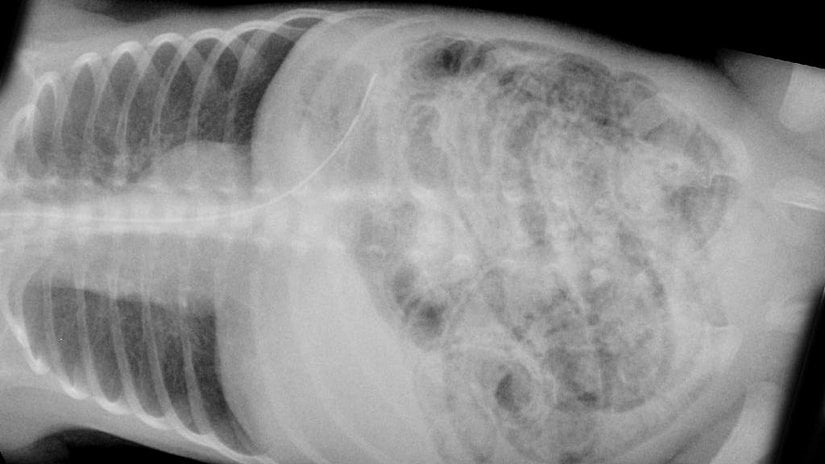

Radyolojik görüntülemede en önemli bulgu, pnömatozis intestinalis adı verilen, bakterilerin fermantasyonu sonucu ortaya çıkan gazın karın iç duvarında birikimidir. Perforasyon, yani organın delinmesi hastalığın en ciddi komplikasyonudur. Taşikardi, hipotermi ve hipotansiyon gibi semptomlar perforasyonun habercisi olabilir. İleri evre hastalarda serebral palsi, görme ve işitme bozuklukları, kognitif bozukluklar, psikomotor gerilik gibi nörolojik morbiditeler görülebilir.

Hastalığın tanısı klinik, laboratuvar ve radyolojik bulguların uzmanlar tarafından incelenmesiyle konulmaktadır. Tanıdaki önemli radyolojik bulgu bağırsak duvarında bakteriler tarafından fermantasyonla üretilen gazın görünümüdür. Radyolojik görüntülemede ultrasonografi, abdominal grafiye göre daha duyarlıdır. Bağırsaklarda delinme olduğunun işareti olan bağırsak sıvısının varlığını kontrol etmek için karın boşluğundan sıvı örneği alınabilir. Alınan sıvıda kahverengi sıvının varlığı veya gram boyamada bakterilerin pozitif çıkması cerrahi müdahale için önemli bulgulardır. Laboratuvar testleri tanıyı koymada tek başına yeterli değildir, hastalığın şiddetinin belirlenmesinde ve izleminde kullanılırlar.[5]